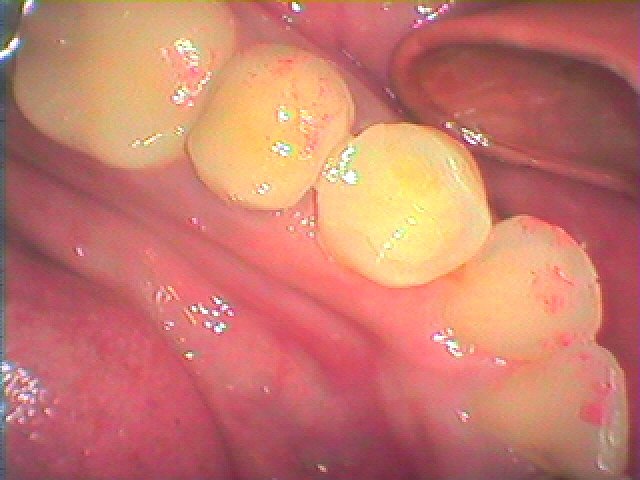

側面ヵら見ても虫歯の大きさがわかります

中が大きく虫歯になっていました